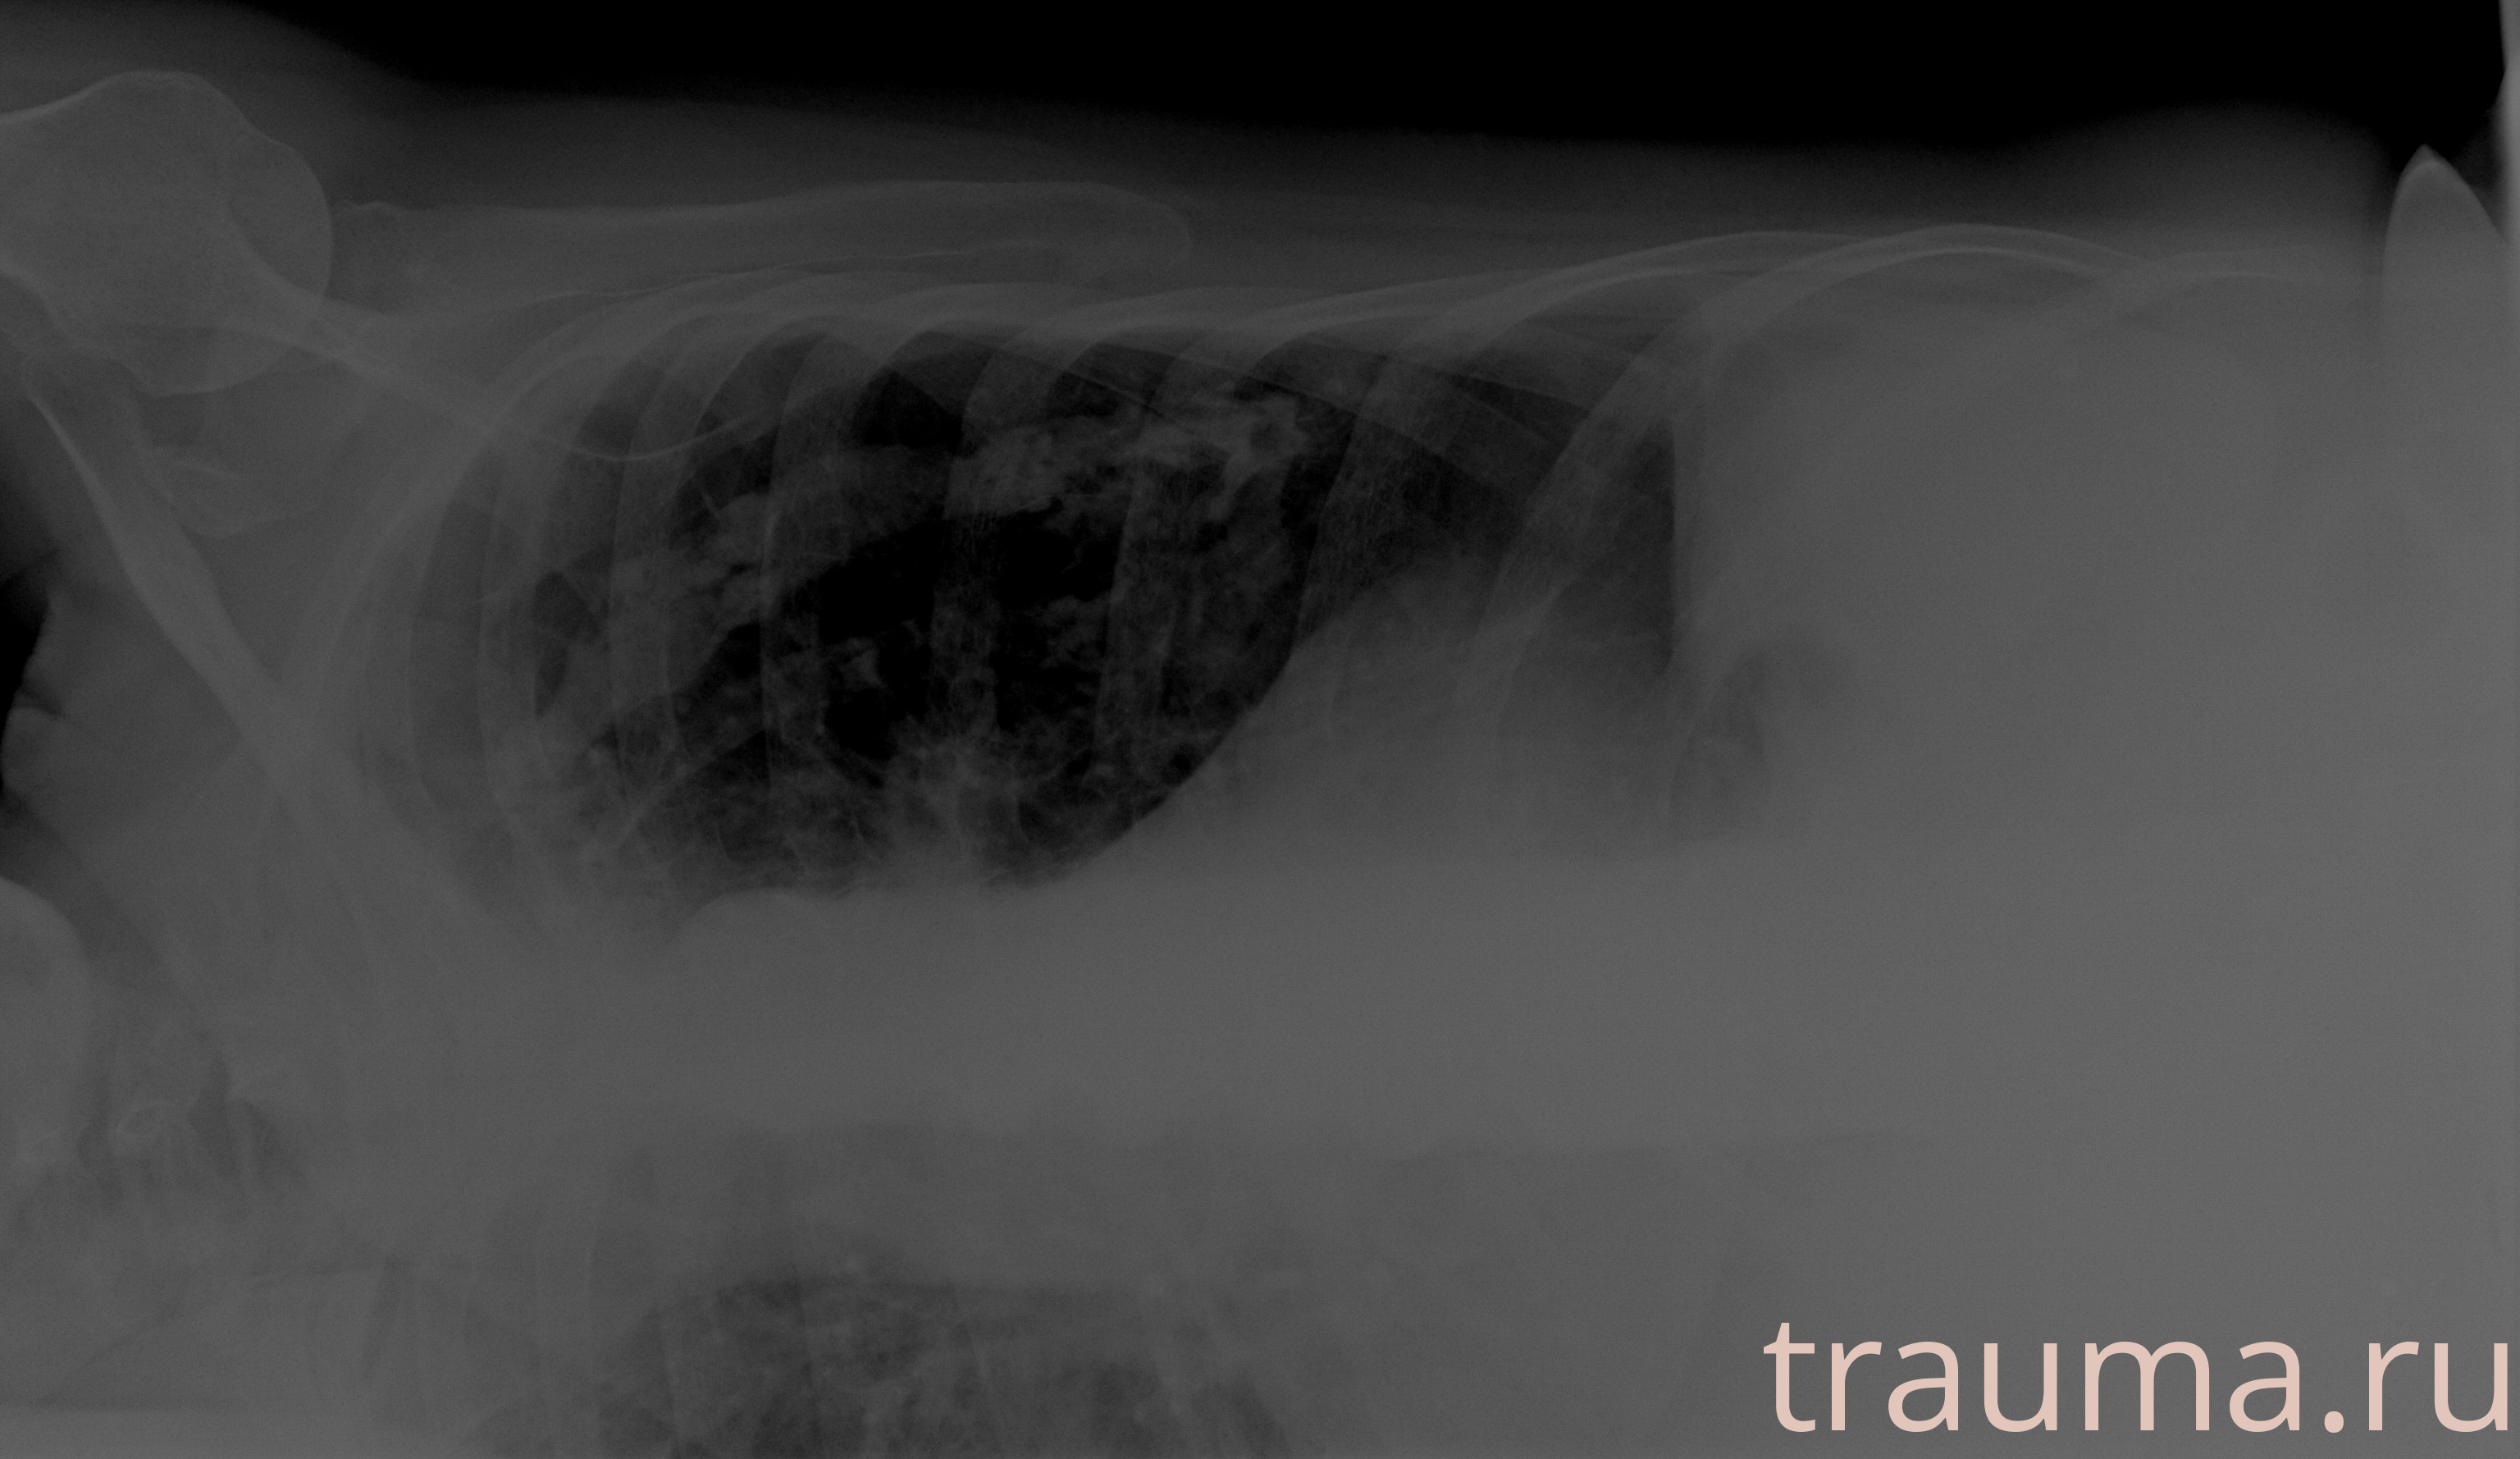

Рентген на дому: по вашему адресу приезжает врач-рентгенолог, травматолог-ортопед с мобильным рентгеновским аппаратом, проводит диагностику травмы или заболевания, делает необходимые рентгенограммы, дает рекомендации по дальнейшему лечению. Получить качественные снимки в домашних условиях возможно благодаря уникальной методике, разработанной МосРентген Центром для института  Склифосовского

при переломе шейки бедра и пневмонии от компании МосРентген Центр - партнера Института имени Склифосовского